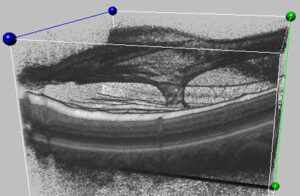

Throughout life the vitreous (the gel-like substance inside the eye) normally liquefies and gradually separates from the retinal surface. Although this usually results in a complete separation of the vitreous (posterior vitreous detachment), it can sometimes remain stuck to the central macula, the specialized area of the retina that gives us our straight-ahead reading and driving vision. Vitreomacular traction occurs when the adherent vitreous tugs and distorts the macula.

Vitrectomy surgery is done in an operating room under local anesthesia. This advanced microsurgical technique restores vision by peeling the adherent vitreous from the macular surface, allowing the underlying macula to smooth out and function more normally. Patients go home immediately following surgery. There is usually minimal to no pain, except for minor irritation. Patients usually notice improved vision with decreased distortion within several weeks to months following vitrectomy although it may take much longer for maximal vision to return. The major surgical side-effect is a cataract, with many patients requiring cataract surgery within a year or two of vitrectomy. There is also a very small chance for secondary retinal detachment or infection.